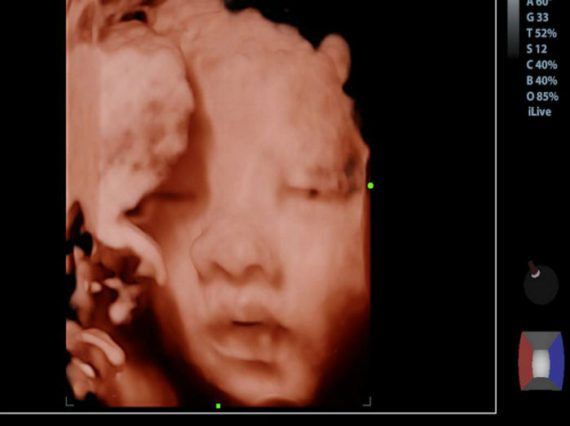

Δείτε τι αισθάνεται το έμβρυο όταν κλαίτε κατά τη διάρκεια της εγκυμοσύνης!

Μια έρευνα αποδεικνύει οτι από τον 6ο μήνα το έμβρυο επηρεάζεται από τα συναισθήματα σας. Και αυτό δεν είναι προσωρινό. Η ψυχική σας υγεία κατά τη διάρκεια της εγκυμοσύνης μπορεί να επηρεάσει τις συνήθειες και τη στάση του εμβρύου για τη ζωή. Και πώς το κλάμα σας επηρεάσει το μωρό σας; Μερικές από αυτές τις κατηγορίες μπορούν να σας βοηθήσουν να καταλάβετε το πώς τα συναισθήματά σας αλλάζουν τη ζωή του μωρού σας – για πάντα.